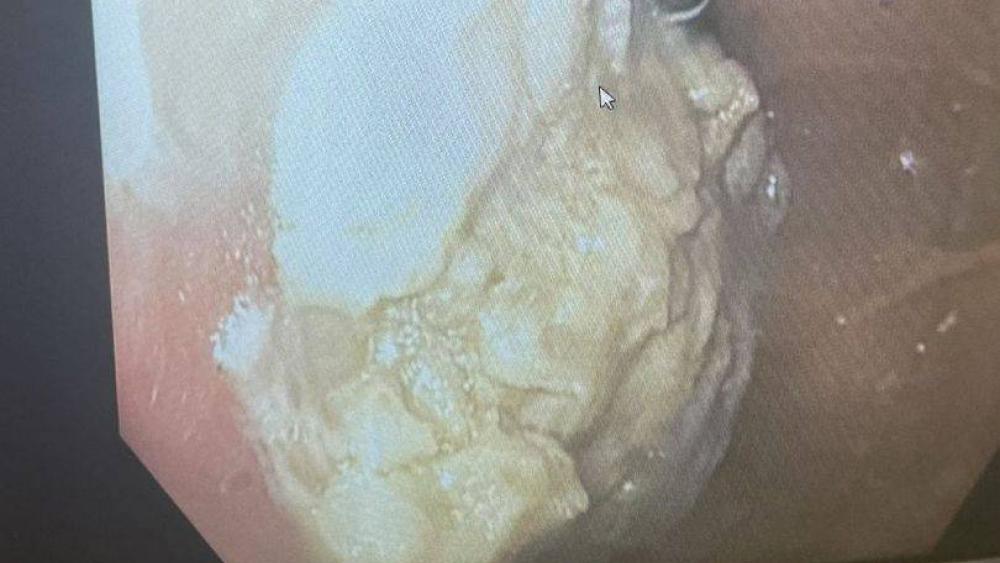

وخاف الأطباء سحب العلكة من المعدة عن طريق التنظير مغبة اختراق جدار الأمعاء الذي قد يؤدي إلى تسرب محتوياتها إلى الجسم، وقرروا إزالة العلكة عبر المريء تحت التخدير.

وقال الأطباء إنهم أجروا العديد من المحاولات لسحب العلكة، واشتكى الطفل بعد العملية من وجود تقرحات في حلقه، ووصف له الأطباء مسكنات للألم لعلاجها، وأخبروه قبل مغادرته المستشفى بأنه محظوظ بأن الكتلة لم تسد أمعاءه، وكان من الممكن أن يفقد حياته.